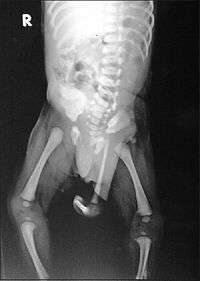

| Radiograph of a human child with polymelia | |

Polymelia (from Greek πολυ- = "many" plus μέλος (plural μέλεα) = "limb") is a birth defect involving limbs (a type of dysmelia), in which the affected individual has more than the usual number of limbs. In humans and most land-dwelling animals, this means having five or more limbs. The extra limb is most commonly shrunken and/or deformed.